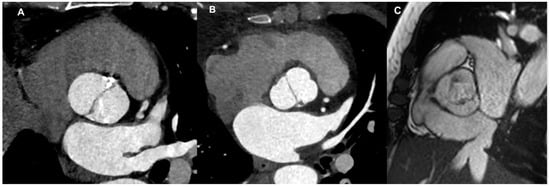

4.1. Aortic Root and Valve Evaluation